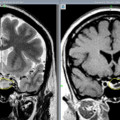

Армянские врачи удалили редко встречающиеся 3-килограммовые метастатические опухоли из яичников пациентки (фото)

В МЦ «Астхик» сотрудничестве с благотворительным фондом «Вива» внедряют новый метод удаления аденом гипофиза